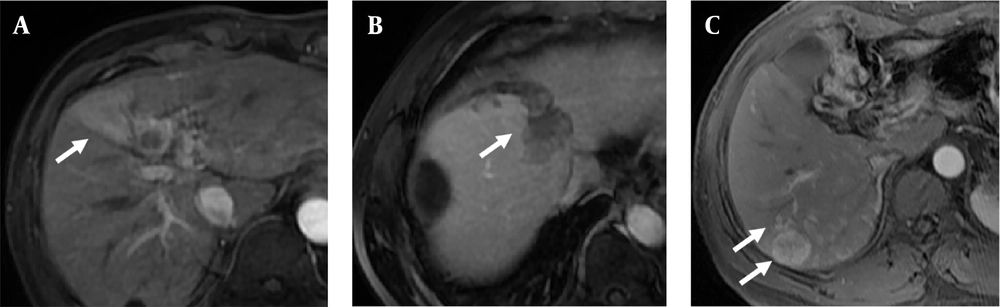

First, we analyzed the correlation of preoperative imaging and clinical characteristics of recurrent tumors with the recurrent tumoral MVI. The results showed that there was no significant difference in age (years, 57.5 ± 8.4 vs. 56.0 ± 8.6, P = 0.457), ALT (U/L, 34.2 ± 23.1 vs. 47.1 ± 50.0, P = 0.230), AST (U/L, 29.9 ± 14.8 vs. 31.2 ± 16.2, P = 0.719), CEA (ng/mL, 2.9 ± 1.8 vs. 2.8 ± 2.0, P = 0.856), CA19-9 (U/mL, 23.4 ± 22.2 vs. 20.0 ± 18.0, P = 0.495), AFP (ng/mL, 221.2 ± 429.3 vs. 154.1 ± 359.8, P = 0.533), neutrophils ( × 109/L, 3.0 ± 0.9 vs. 3.0 ± 0.9, P = 0.727), lymphocytes ( × 109/L, 1.6 ± 0.5 vs. 1.6 ± 0.4, P = 0.761), monocytes ( × 109/L, 0.4 ± 0.1 vs. 0.4 ± 0.1, P = 0.769), eosinophils ( × 109/L, 0.1 ± 0.1 vs. 0.1 ± 0.1, P = 0.870), basophils ( × 109/L, 0.0 ± 0.0 vs. 0.0 ± 0.0, P = 0.725), and size (cm, 3.1 ± 2.0 vs. 2.7 ± 1.6, P = 0.350) between the recurrent tumoral MVI-negative and positive groups. Among imaging characteristics, arterial peritumoral enhancement, non-smooth margin, and multifocality were correlated with MVI in recurrent tumors, as shown in Figure 2A - C, respectively. Using these, we constructed model 1 to predict MVI in recurrent tumors.